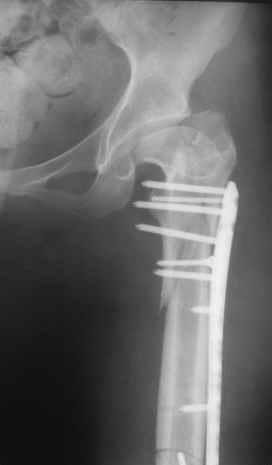

Уважаемые коллеги, приношу извенения за молчание. Готовили материал и боялись писать раньше времени. Все хотели убедиться в том, что после операции все будет спокойно. Спасибо за отклики и советы. К сожалению, гамма-гвоздя, штифтов с возможностью установки более 2-х блокирующих винтов у нас нет. Зато нашли достаточно длинную пластину с угловой стабильностью. После проведения предоперационной подготовки и планирования выполнили остеосинтез. В условиях рентгеноперационной, после репозиции дистрактором из одного разреза 5см в проксимальном отделе подкожно установили пластину. Пришлось выполнить дополнительный разрез до5см в проекции перелома диафиза в средней трети, из которого удалось репонировать перелом и выполнить фиксацию стягивающим винтом. Затем все завершилось наложением пластины с угловой стабильностью. Пластина оказалась достаточно длинной, что позволило перекрыть все переломы с фиксацией каждого отломка минимум 5-ю винтами. Синтез достаточно стабилен. Пациентка активизирована на 3-и сутки(снимки прилагаются). В настоящий момент пациентка выписана на амбулаторное лечение. Еще раз, огромное спасибо всем за помощь в выборе тактики и просто совете. С уважением Украинский Е.

Получилось очень симпатично, мои поздравления. А можно фото конечности без наклеек посмотреть?

И межфрагментарный винт на диафизе - так ли он нужен при выбранном варианте остеосинтеза с относительной стабильностью?

Хотя все-таки закрыто антгерадно заштифтовать тут было вполне можно, и при использовании отечетственного имплантата лечение обошлось бы на порядок дешевле. Опасения коллеги Кульджанова насчет кровоснабжения головки бедра и предстоящих операции в этой области кажуься несколько

преувеличенными - и стержень можно через вертел ввести, да и расстройства кровоснабжения головки, если они случатся после штифтования, не будут длиться вечно.

Но в люом случае, что сделано - то сделано, и сделанное выглядит вполне обнадеживающе, так что еще раз поздравляю коллег с успешным выходом из непростой ситуации.